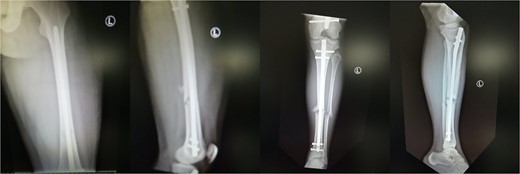

As soon as the patient woke up from the general anesthesia, he reported severe pain of the right uninjured calf. After 3 h, the pain became worse and unresponsive to strong analgesic medications. On examination, extreme swelling in the right calf was noticed. The pain was exacerbated with passive movements of the right toes and ankle. A progressive weakness of the anterior tibialis and the extensor hallucis longus muscle was noticed as well. The diagnosis of the right uninjured tibia compartment syndrome owing to the lithotomy position was confirmed and the patient underwent the appropriate fasciotomies 6 h after the initial operation. The shoelace surgical technique (Fig. 3) was performed for gradual closure of the compartments. Six months post-operation, the patient has gained 5/5 motor strength of the anterior tibialis and 3/5 of the extensor hallucis longus muscle, with no sensory deficits. A left femoral and tibia nail dynamization has been performed because of the fracture delayed union.

Progressive closure of the right uninjured tibia open compartments using the shoelace technique.